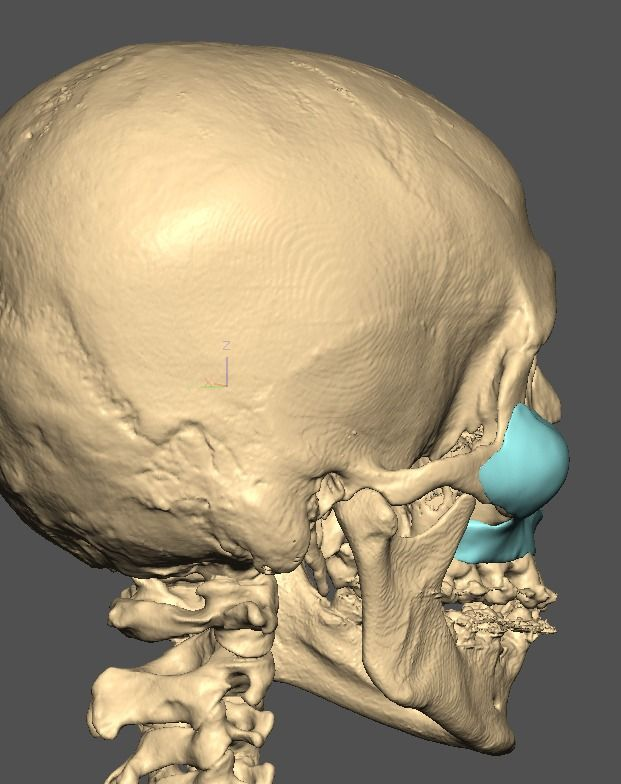

I know a guy who designed this for himself in collaboration with an asian implant company.

Not the final product yet, he is making adjustments as we speak.

Found a surgeon willing to insert it.

Giant and Eppley were the inspiration